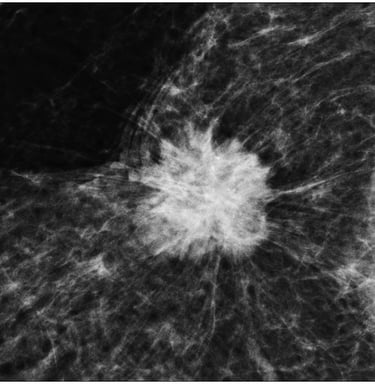

Spiküle Kitle: LR (+) > 20.0.

Luminal A Dominansı: Spiküle (kenarları ışınsal uzantılı) kitlelerin %71'i Luminal A alt tipi olarak sınıflandırılmıştır.

Olasılık Oranı (Odds Ratio): Luminal A alt tipindeki kitlelerin, diğer alt tiplere oranla mamografide spiküle görünüm sergileme olasılığı 10.3 kat daha fazladır (p < 0.001).

Biyobelirteç Korelasyonu: Spiküle görünümün en güçlü öngörücüleri Düşük Ki67 indeksi (< %14) ve HER2 negatifliğidir. Hormon reseptör (ER/PR) pozitifliği de ilişkili bulunmuştur ancak etkisi Ki67 ve HER2 kadar baskın değildir.

İyi Prognoz İşareti: Spiküle marjlar, genellikle tümör hücrelerinin çevre dokuyla (stroma/yağ dokusu) etkileşimini ve düşük dereceli (low-grade) progresyonu gösterir. Bu durum, spiküle kitlelerin neden daha iyi bir prognoza işaret ettiğini açıklar.

Tanısal Doğrulama: Eğer bir tümör mamografide spiküle görünüyorsa ancak patolojide "HER2 pozitif" geliyorsa, bu bir uyumsuzluk (discordance) bayrağıdır; testin tekrarı düşünülebilir.

Mamografide görülen spiküle kitle, invaziv meme kanserinin Luminal A alt tipi için güçlü bir radyolojik belirteçtir. Bu korelasyonun temelinde tümörün düşük proliferatif aktivitesi (Ki67) ve HER2 gen ekspresyonunun olmaması yatar. Bu veriler, "spiküle kitle" verisinin, biyopsi öncesi Luminal A olasılığını (prior probability) belirgin şekilde yükselttiğini kanıtlamaktadır.